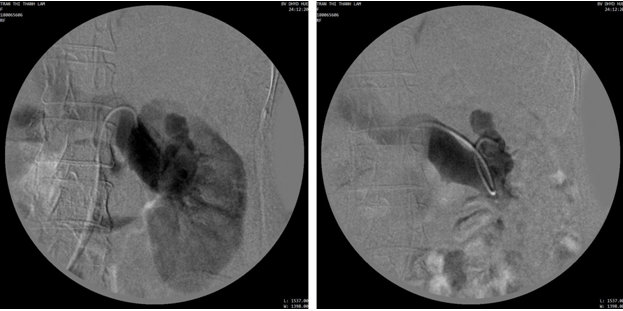

Hình 2. Chụp mạch số hóa xóa nền (DSA) động mạch thận trái: Luồn thông trực tiếp từ nhánh động mạch thùy trên và tĩnh mạch thận có đường vào ngoằn ngoèo. Chụp chọn lọc luồn thông thấy nhiều túi phình, giãn lớn tĩnh mạch thận trái chứng tỏ luồn thông có dòng chảy cao.